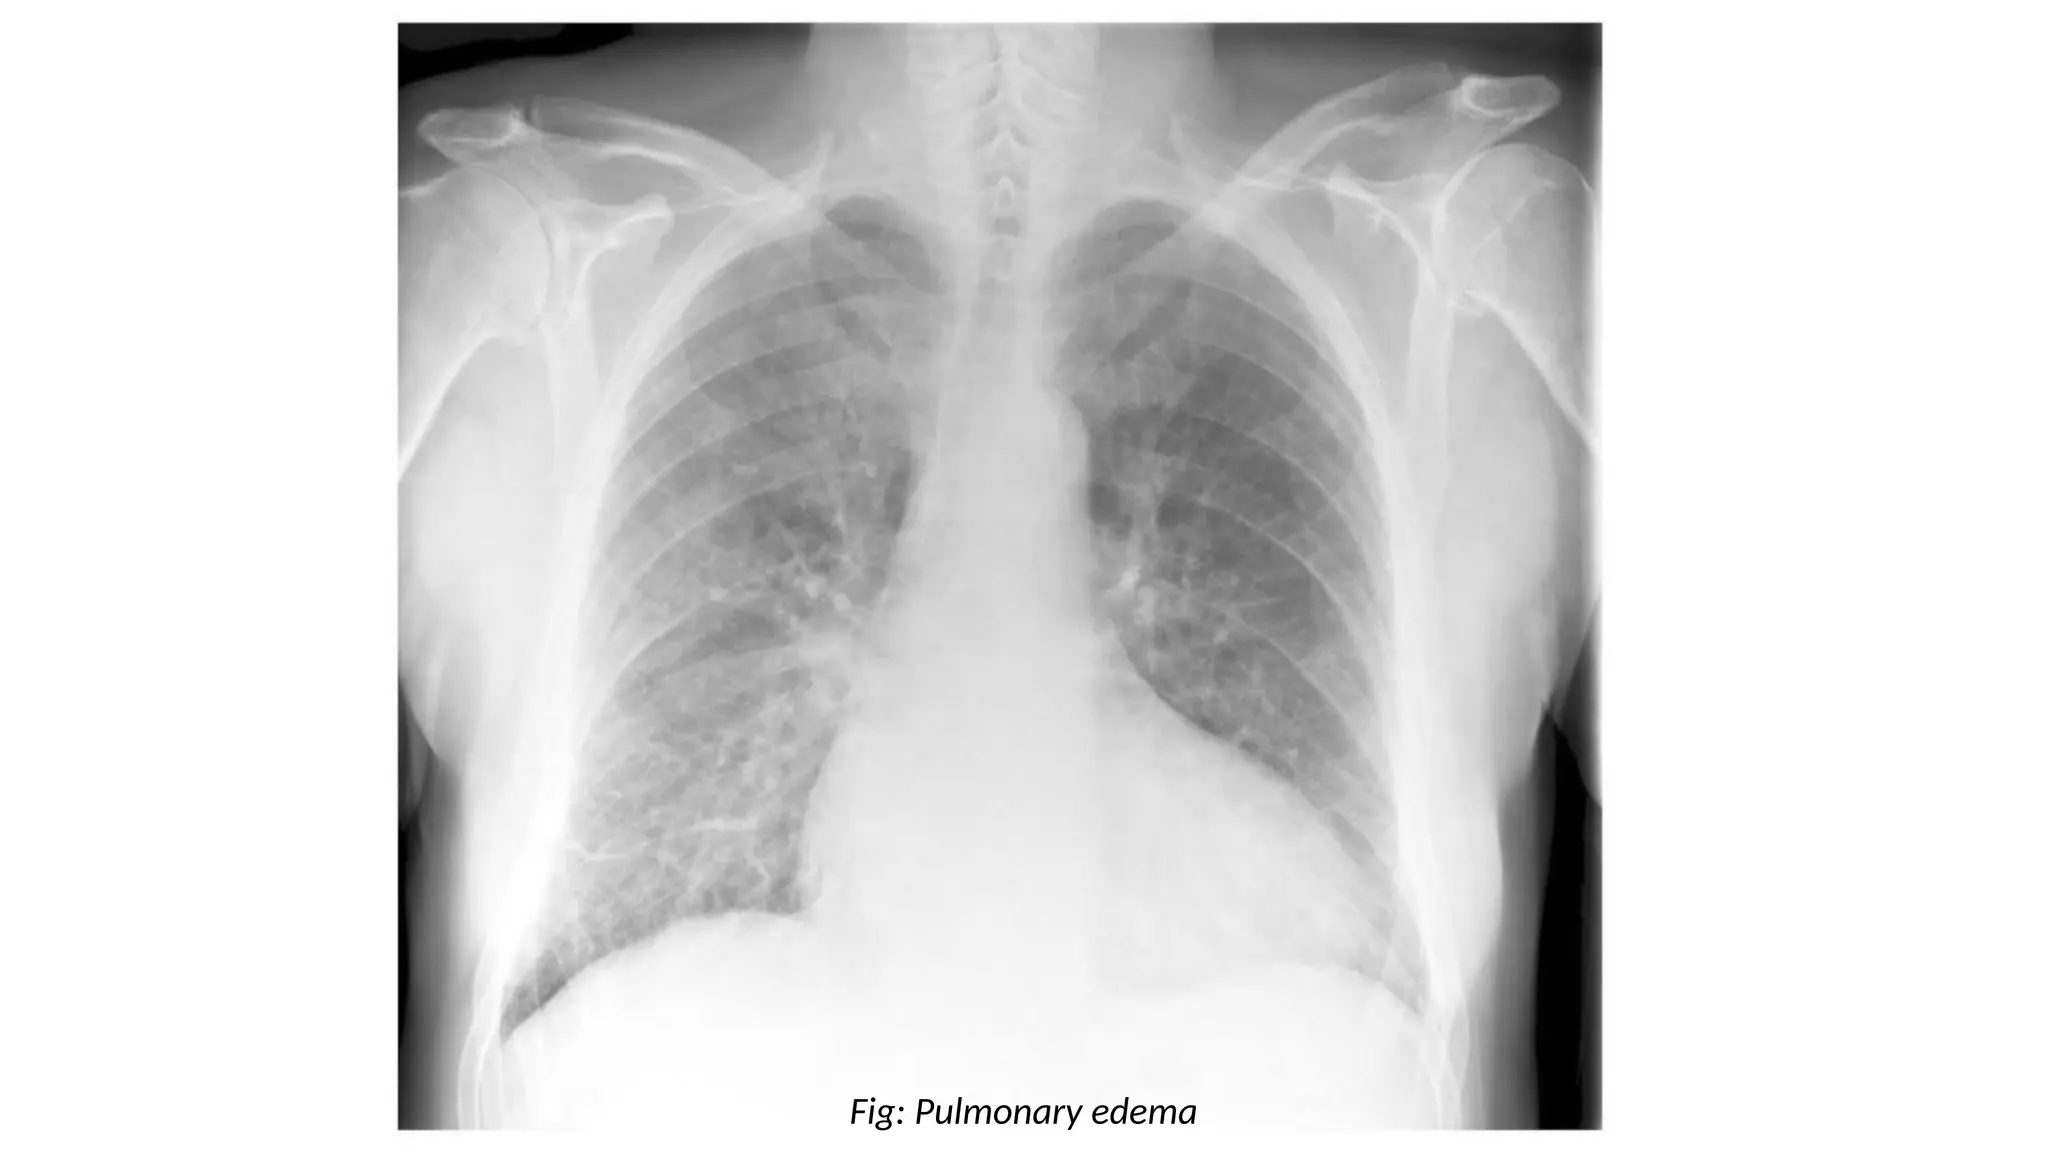

Pulmonary Edema

• Common findings may include:

Air space opacification (bat wing distribution)

Kerley B lines

Pleural effusions (look for costophrenic blunting)

Fluid in interlobular fissures

Fig: Pulmonary edema

• Common causes of pulmonary edema includes:

Left heart failure

Mitral regurgitation

Fluid overload